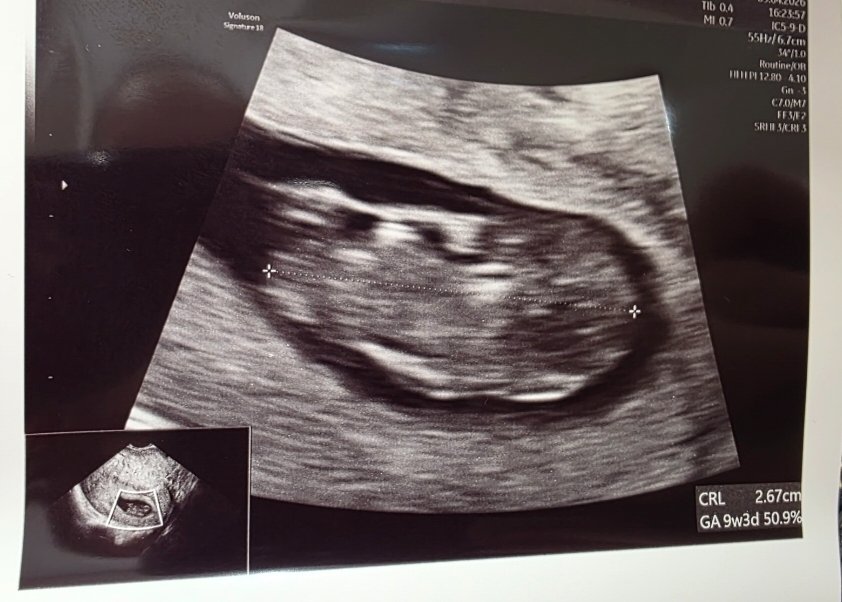

U nas mały człowieczek ma 2,6cm❤️❤️❤️

Serduszko 169ud/min.